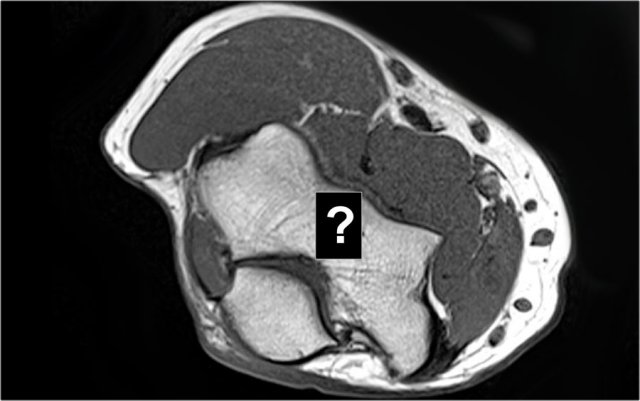

Pseudo-loose body

Another common finding is a small piece of fat that you'll see on the sagittal image, that looks like a small loose body or a cartilage defect.

This can be explained if we look at the articular surface of the olecranon.

Typically the olecranon has two pieces of cartilage with a small area inbetween, that fills with fat.

What is the structure on the axial image behind the radial head?

The structure behind the radial head is the annular ligament.

It is irregular and thickened as a result of the posterior dislocation.